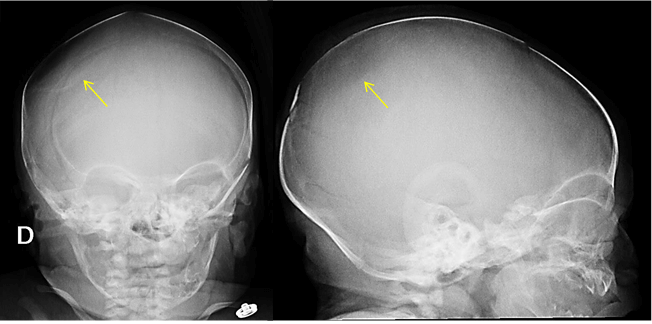

Question :A male term newborn was delivered at 39 weeks of gestation from a 43-year-old woman by an urgent caesarean for fetal bradycardia. Pregnancy was complicated with gestacional diabetes controlled with metformin. Fetal ultrasounds were normal and there was no history of prenatal maternal trauma. The fetus was difficult to extract but no obstetric instruments were used during delievery. He adapted well with an Apgar score of 9 and 10 at first and fifth minutes, respectively. Somatometry at birth was adequate for gestational age: weight of 3500g (50th percentile), length of 48 cm (15th-50th percentile) and head circumference of 35,5 cm (50th-85th percentile). Postbirth physical examination revealed a depression in the right parietal region measuring 4 x 3 cm with 2 cm depth (Figure 1). No local bruising or soft tissue swelling was evident. His neurological examination was normal and there were no other congenital abnormalities.

Figure 1. Depression in the newborn’s right parietal bone (at birth).  What is the diagnosis?